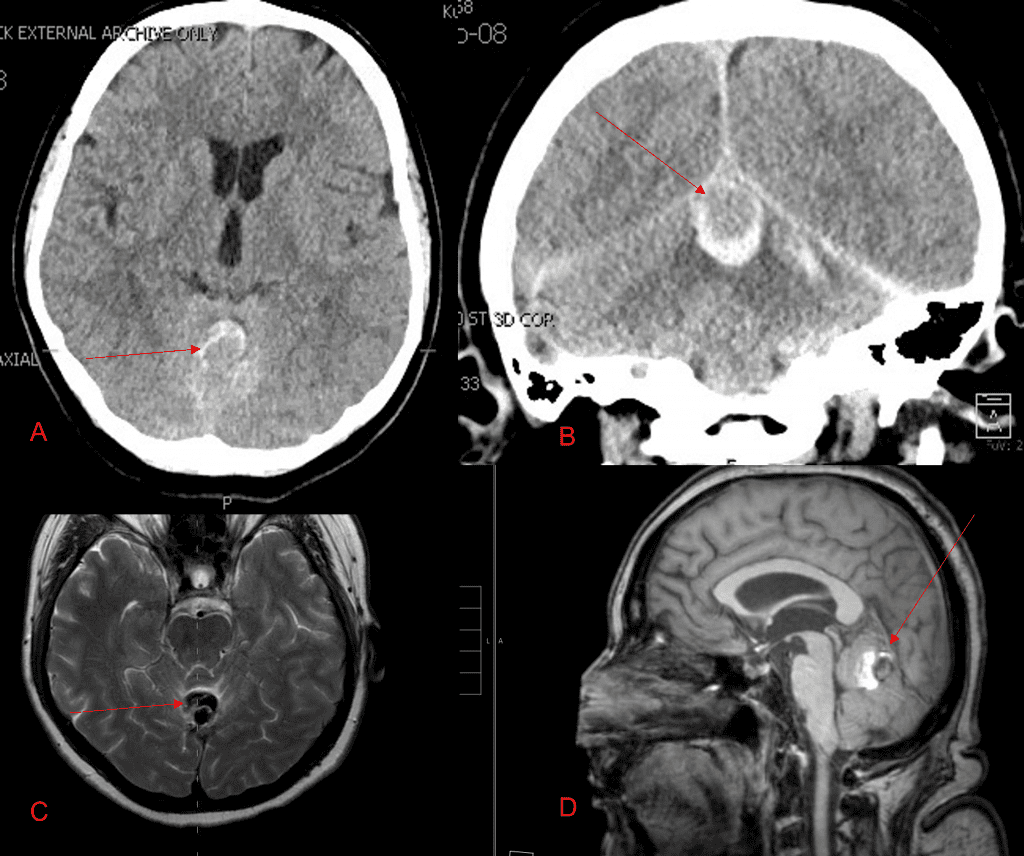

Brain:

Cerebellar Hemangioblastoma

Author: Michael Brisman M.D., F.A.C.S., Read More!